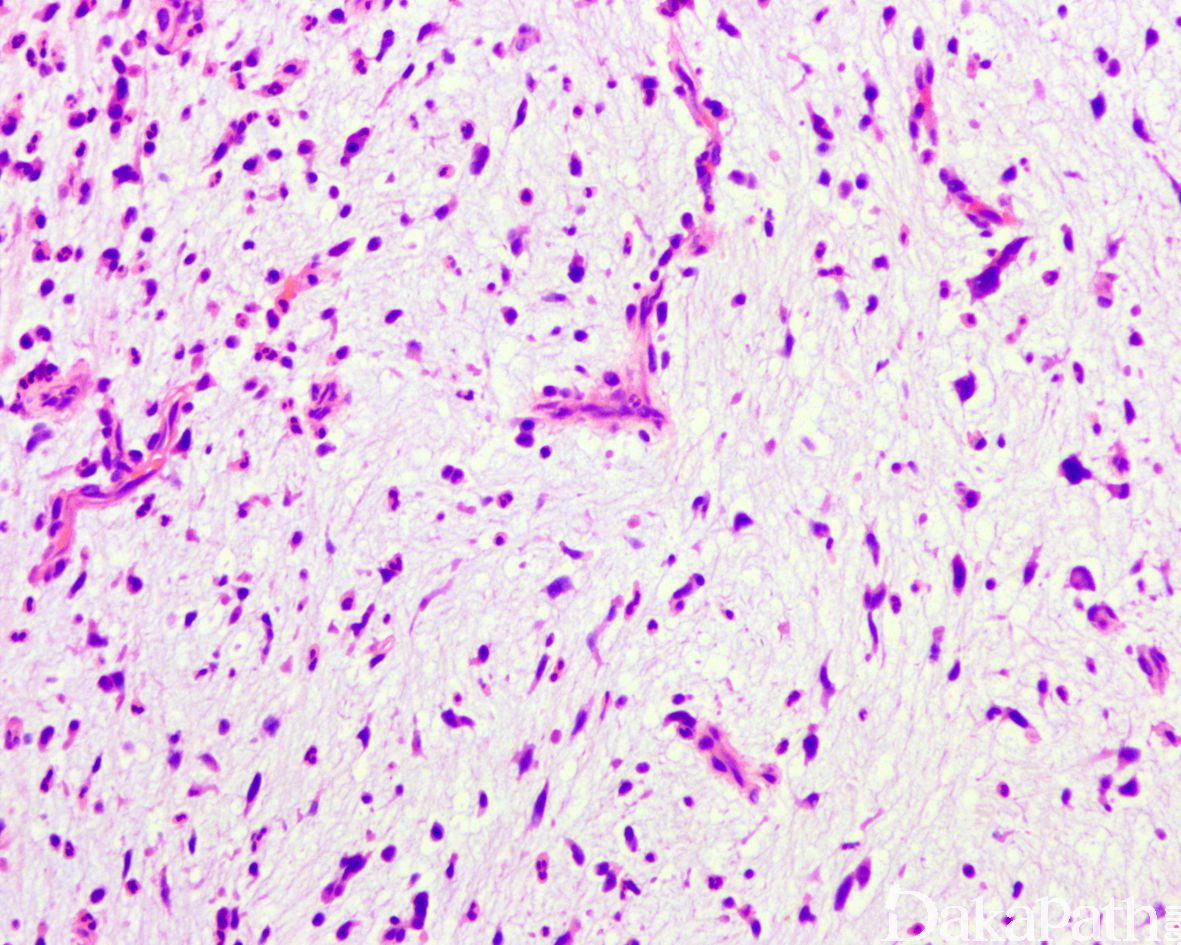

组织形态学上,软组织血管纤维瘤具有特征性的形态学特点:温和的纤维母细胞样瘤细胞,数目众多的分支状薄壁小血管以及比例多少不等的粘液水肿或胶原性基质;

大多数肿瘤界限清楚,部分带包膜,有时可见包膜周淋巴小结聚集伴生发中心形成。瘤细胞短梭形或星芒状,核形态温和,在粘液变显著的情况下偶见退行性核改变;核分裂像罕见。大多数病例肿瘤细胞呈无结构方式随意分布,部分病例可见围绕鹿角状薄壁静脉呈血管外皮细胞瘤样排列。瘤细胞密度一般较均匀,区域内瘤细胞密度增加形成富于细胞灶,与少细胞区交替分布,两者逐渐或突然过渡。病变的另一特征性表现为弥漫分布于肿瘤内的薄壁分支状小血管,有时可互相连接形成网状结构,偶尔血管壁周围可见玻璃样变性。